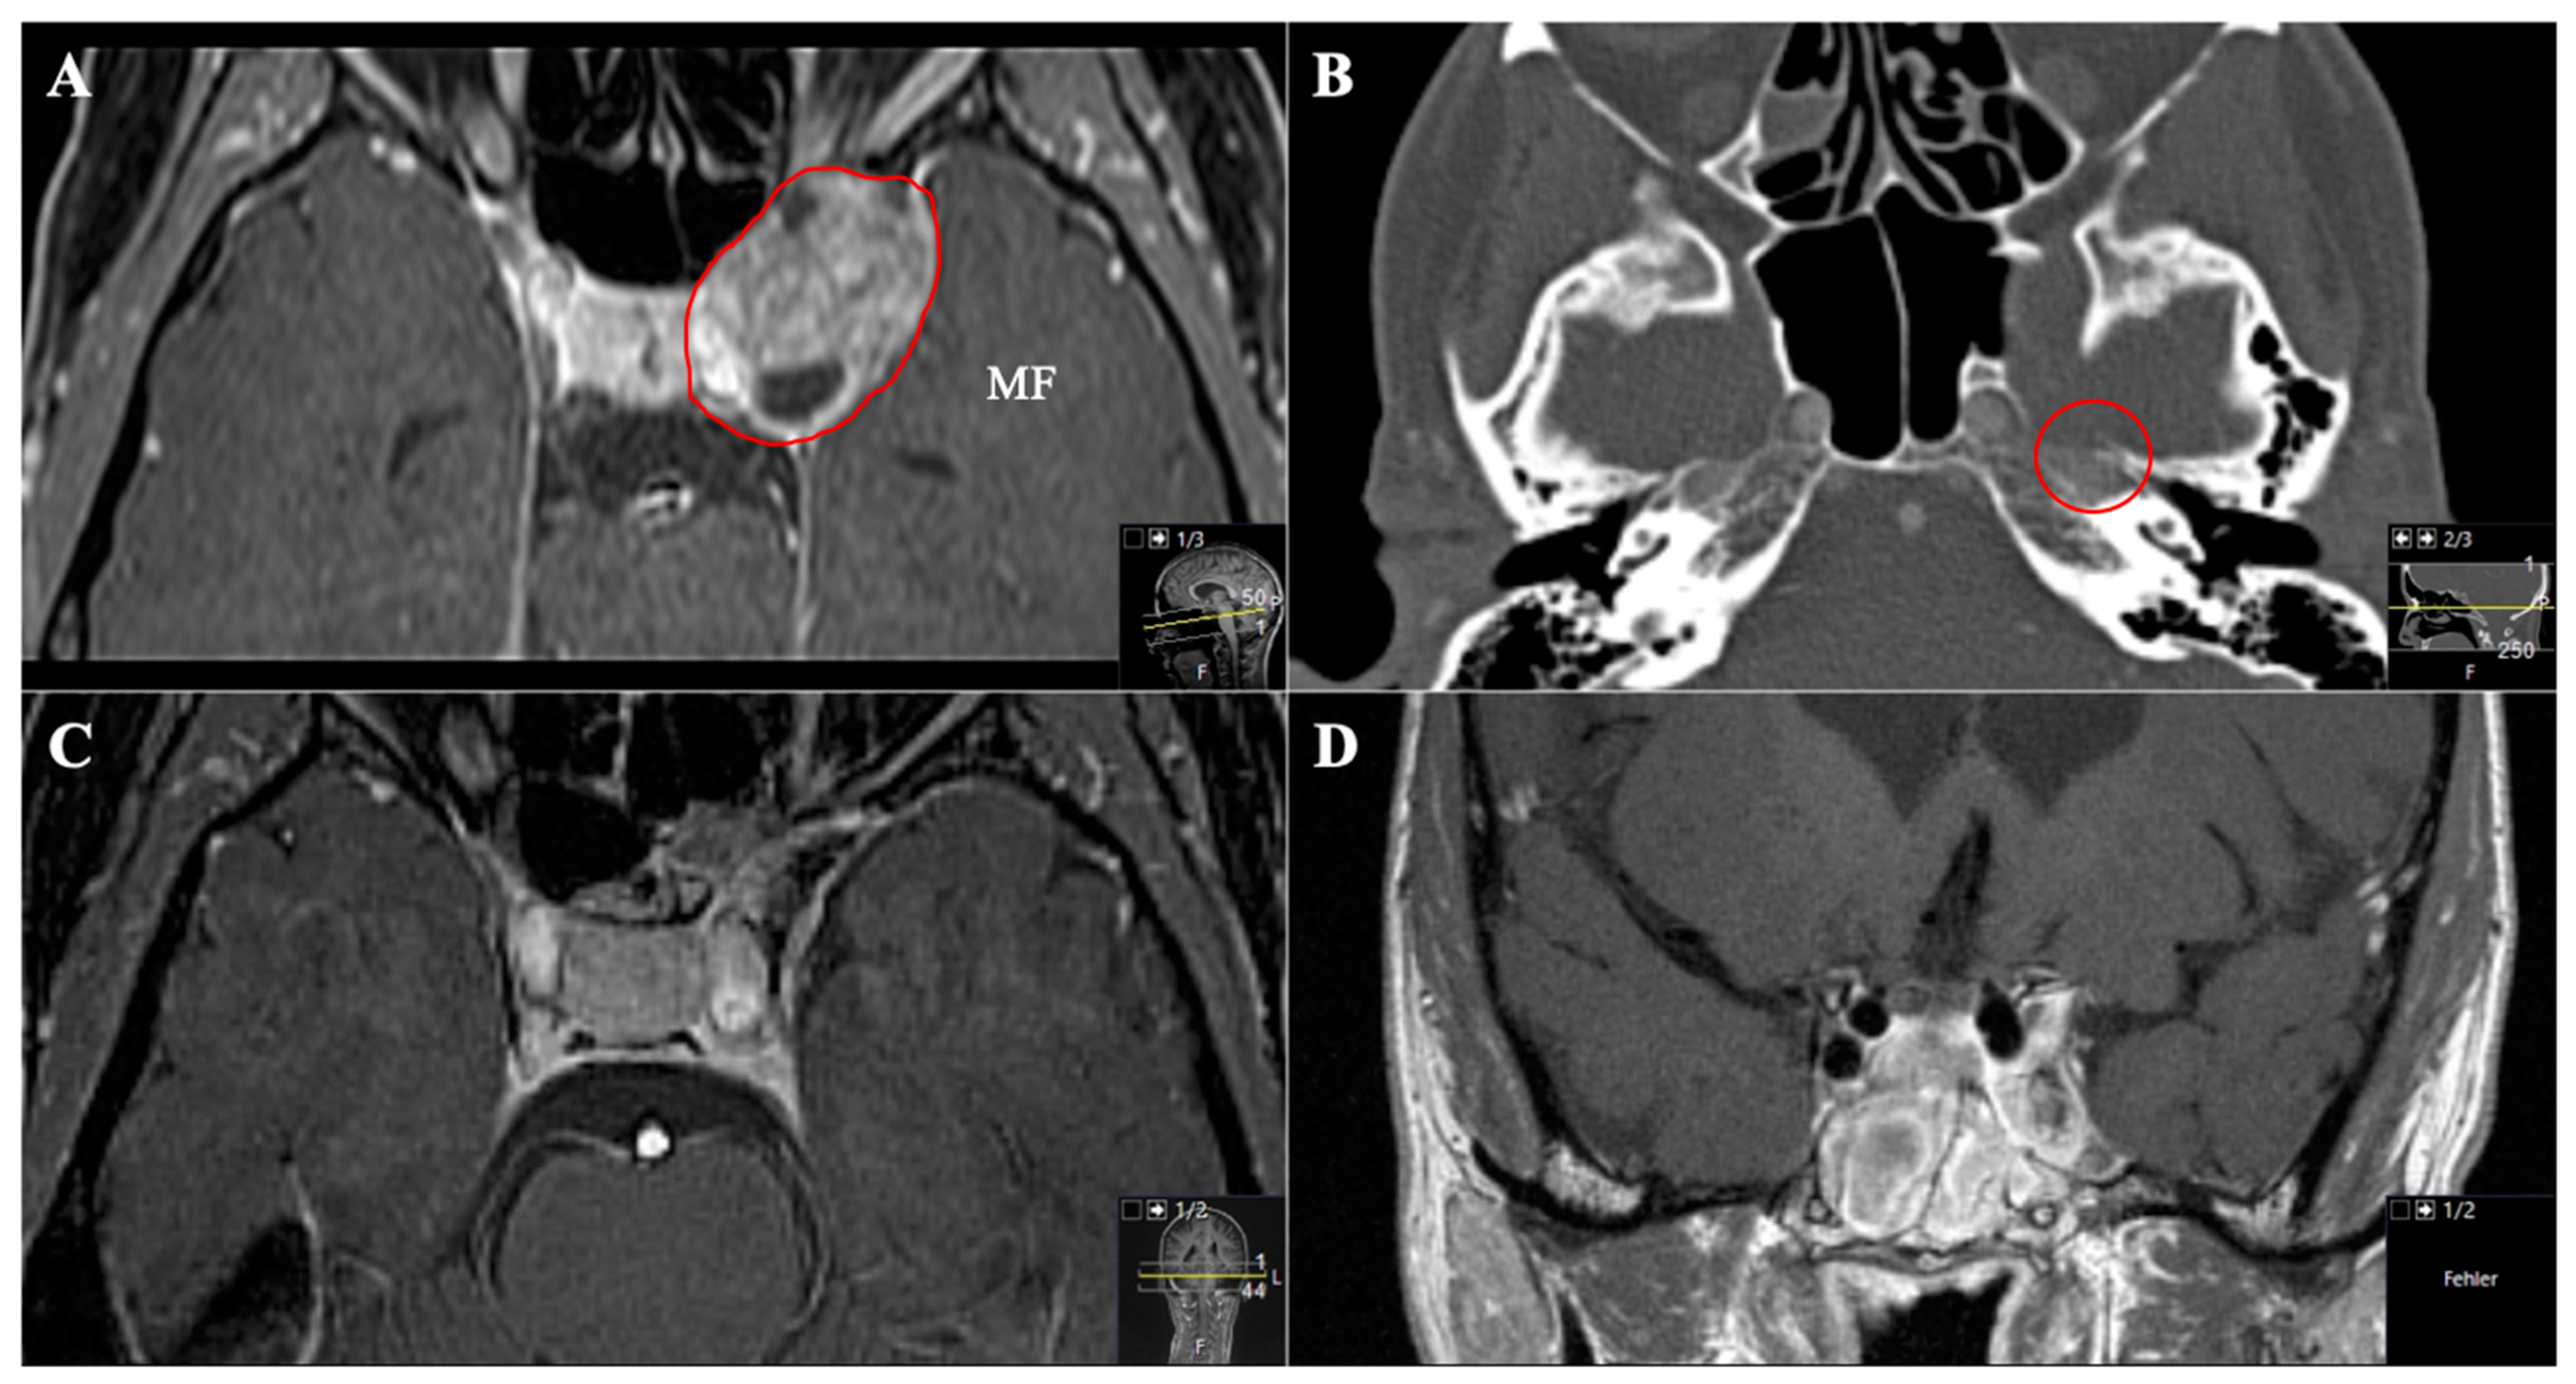

Figure 9. A 54-year-old female patient presented with slowly progressive visual impairment on the left side, trigeminal hypesthesia (V3) and an abducens nerve palsy with intermittent facial pain. (AC) Preoperative axial T1-weighted gadolinium-enhanced MRI showing a massive space-occupying mainly extracranial trigeminal schwannoma (Type D) involving the middle fossa up to the orbital funnel. The schwannoma is bounded medially by the lamina papyracea, inferiorly by the hard palate and infiltrating the pterygopalatine fossa laterally. The middle nasal concha forms the anterior border. The paranasal sinuses are completely misplaced. (DF) Preoperative axial CT scans demonstrating the destruction of the anterior skull base including the orbital funnel, the foramina ovale and rotundum and also the nasal septum and the maxillary sinus (arrows).

Figure 10. Postoperative outcome and MRI control (see Figure 9) (AC) Postoperative axial T1-weighted gadolinium-enhanced MRI showing a satisfactory STR with small remnants in the maxillary sinus (arrows in (B)). Resection was performed by an endoscopic transnasal approach using the tumor-related widened corridor to the maxillary sinus. The patient recovered very well, the visual impairment recovered subsequently, the abducens nerve palsy and the facial pain during follow-up as well. The trigeminal hypesthesia remained. The patient had follow-up controls without any progress.